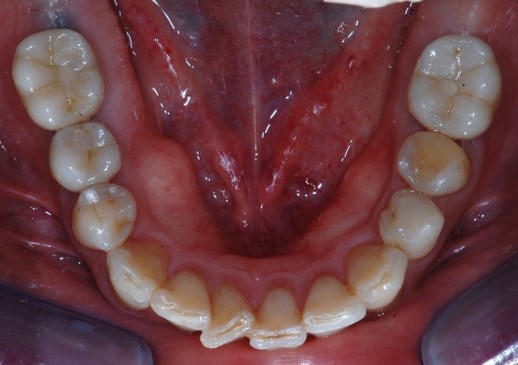

A distanza di circa una settimana dalla scansione il paziente veniva fatto venire nuovamente in studio per la consegna delle tre corone definitive avvitate e completare così la riabilitazione implanto-protesica (Figure 13, 14).

Fig. 14. Consegna delle corone avvitate.